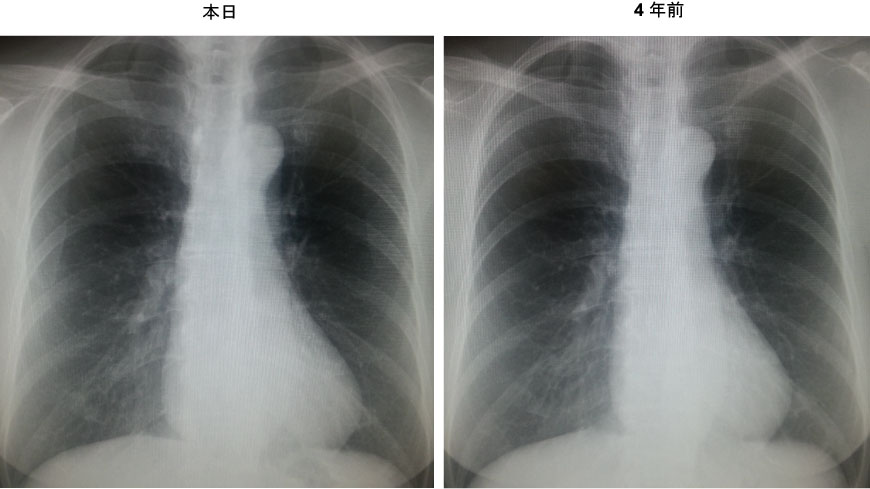

70歳。女性。人間ドック受診した。

・胸部Xp:右上肺野に円形陰影出現

・胸部CTで石灰化肉芽腫、瘢痕の診断。